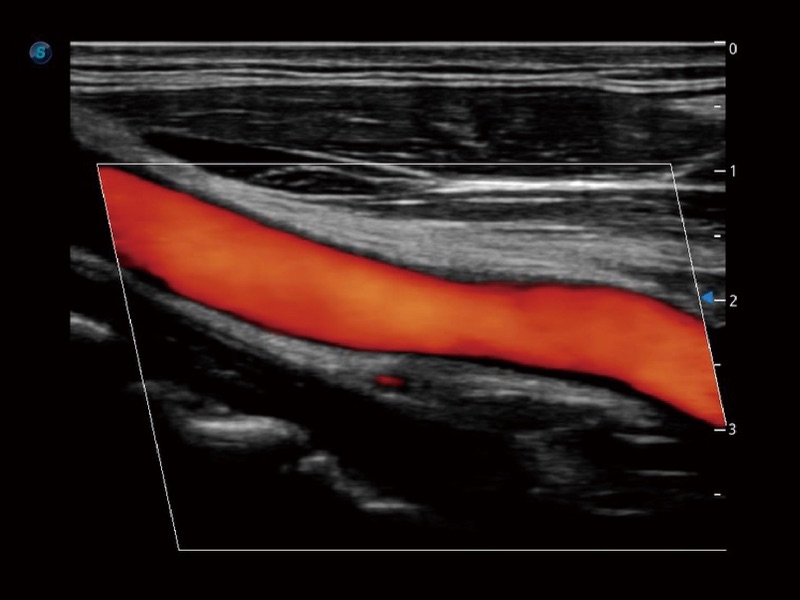

血管内中膜的厚度值是预测心血管疾病风险的重要指标,Auto IMT可以实现血管近场和远场内中膜厚度的自动测量,为临床提供快捷有效的诊断工具。